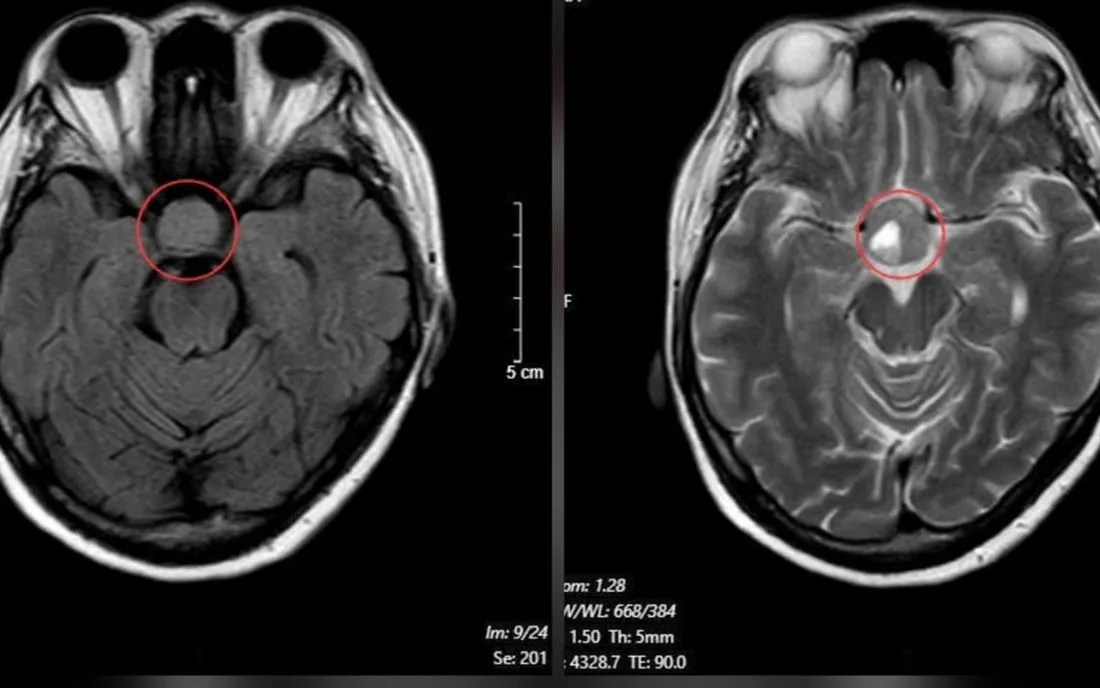

Từ các dấu hiệu này, người bệnh được chỉ định chụp cộng hưởng từ (MRI) sọ não. Kết quả phát hiện khối u tuyến yên kích thước lớn (macroadenoma), đo được khoảng 26x21 mm, chèn ép giao thoa thị giác. Người bệnh sau đó được chuyển đến chuyên khoa Phẫu thuật Thần kinh để tư vấn và lên kế hoạch điều trị nhằm phòng ngừa nguy cơ mất thị lực không hồi phục và các biến chứng thần kinh khác.